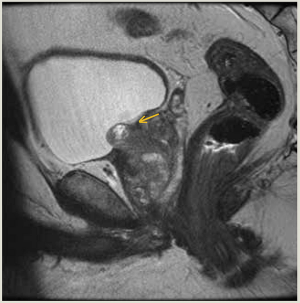

This is the case of a man, aged 56 years, who presented with urinary intermittency, frequency, urgency, and dysuria 5 months after undergoing focal laser ablation (FLA) of Gleason 3 + 4 = 7 prostate cancer (PC).